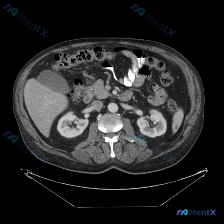

- 扫描层面:仅上腹部,显示肝右叶部分、胆囊、双肾、胰腺、血管、胃及肠管

- 强化状态:增强扫描(血管强化明显),软组织窗对比度好

- 核心关键:此层面未显示完整脾脏,仅见部分脾边缘,且密度均匀

- 其他:肝、胆、胰、双肾、腹膜后、胃肠道均未见明确异常